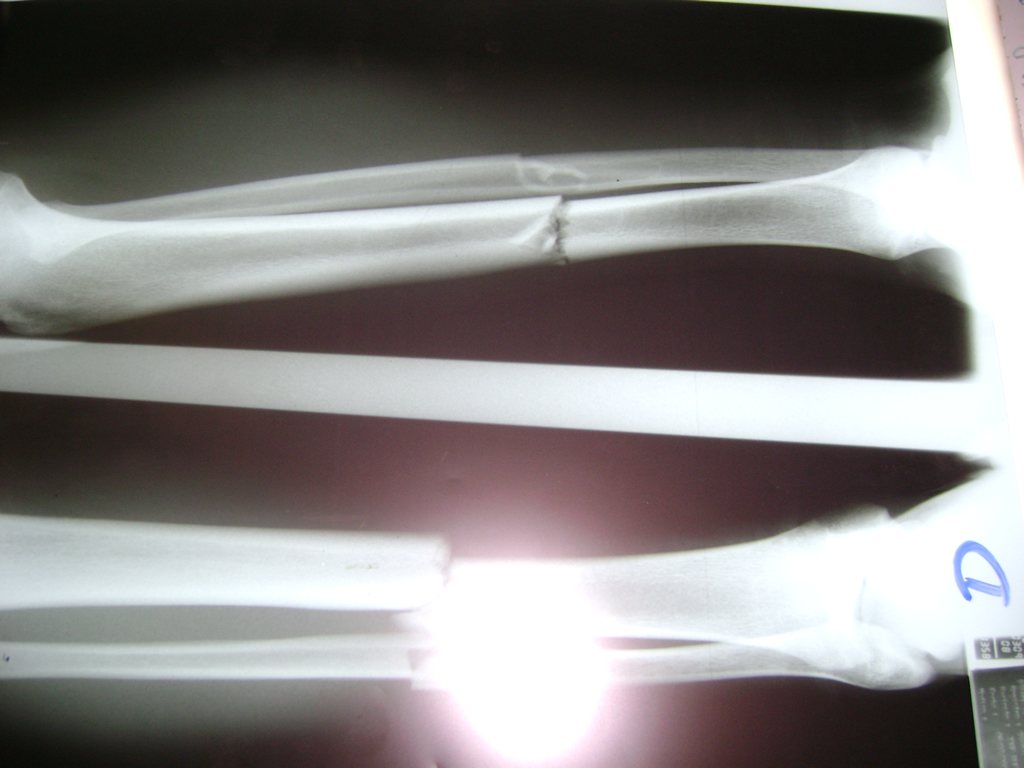

Calcaneo - Perone y Tibia

Aunque cada uno de estos huesos puede fracturarse por separado, normalmente la rotura es una lesión que se produce de forma conjunta

La mayor parte de las roturas implican a la parte proximal del hueso (parte del hueso próximo a la rodilla) o a la parte distal (parte del hueso cerca del tobillo).

Debido a la fina cobertura de piel que recubre la tibia y el peroné, las fracturas generalmente son abiertas, es decir, el hueso roto rasga la piel, atravesándola. Las fracturas de tibia y peroné generalmente se producen por un fuerte impacto o torsión.